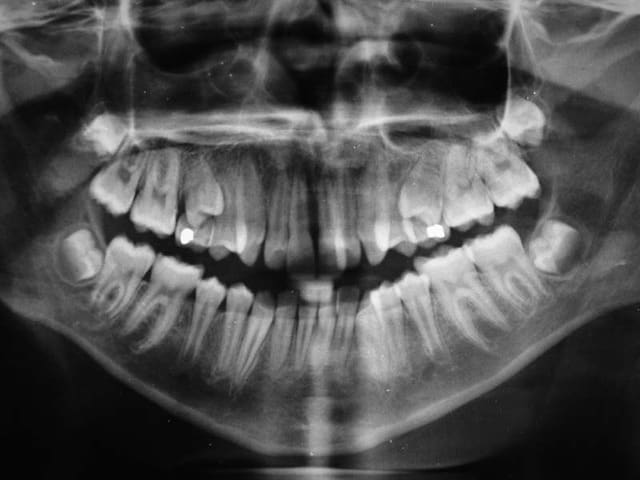

Bjc.

complément Rx. demandés

@+ Bjc.